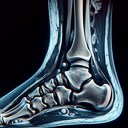

МРТ гомілково-ступневогу суглобу

Магнітно-резонансна томографія (МРТ) гомілково-ступневого суглоба — це неінвазивне дослідження, яке використовує магнітні поля та радіохвилі для створення детальних зображень суглоба та навколишніх тканин. **Переваги МРТ:** 1. **Висока точність:** Дозволяє детально оцінити стан кісток, хрящів, зв'язок, сухожиль та м'яких тканин...